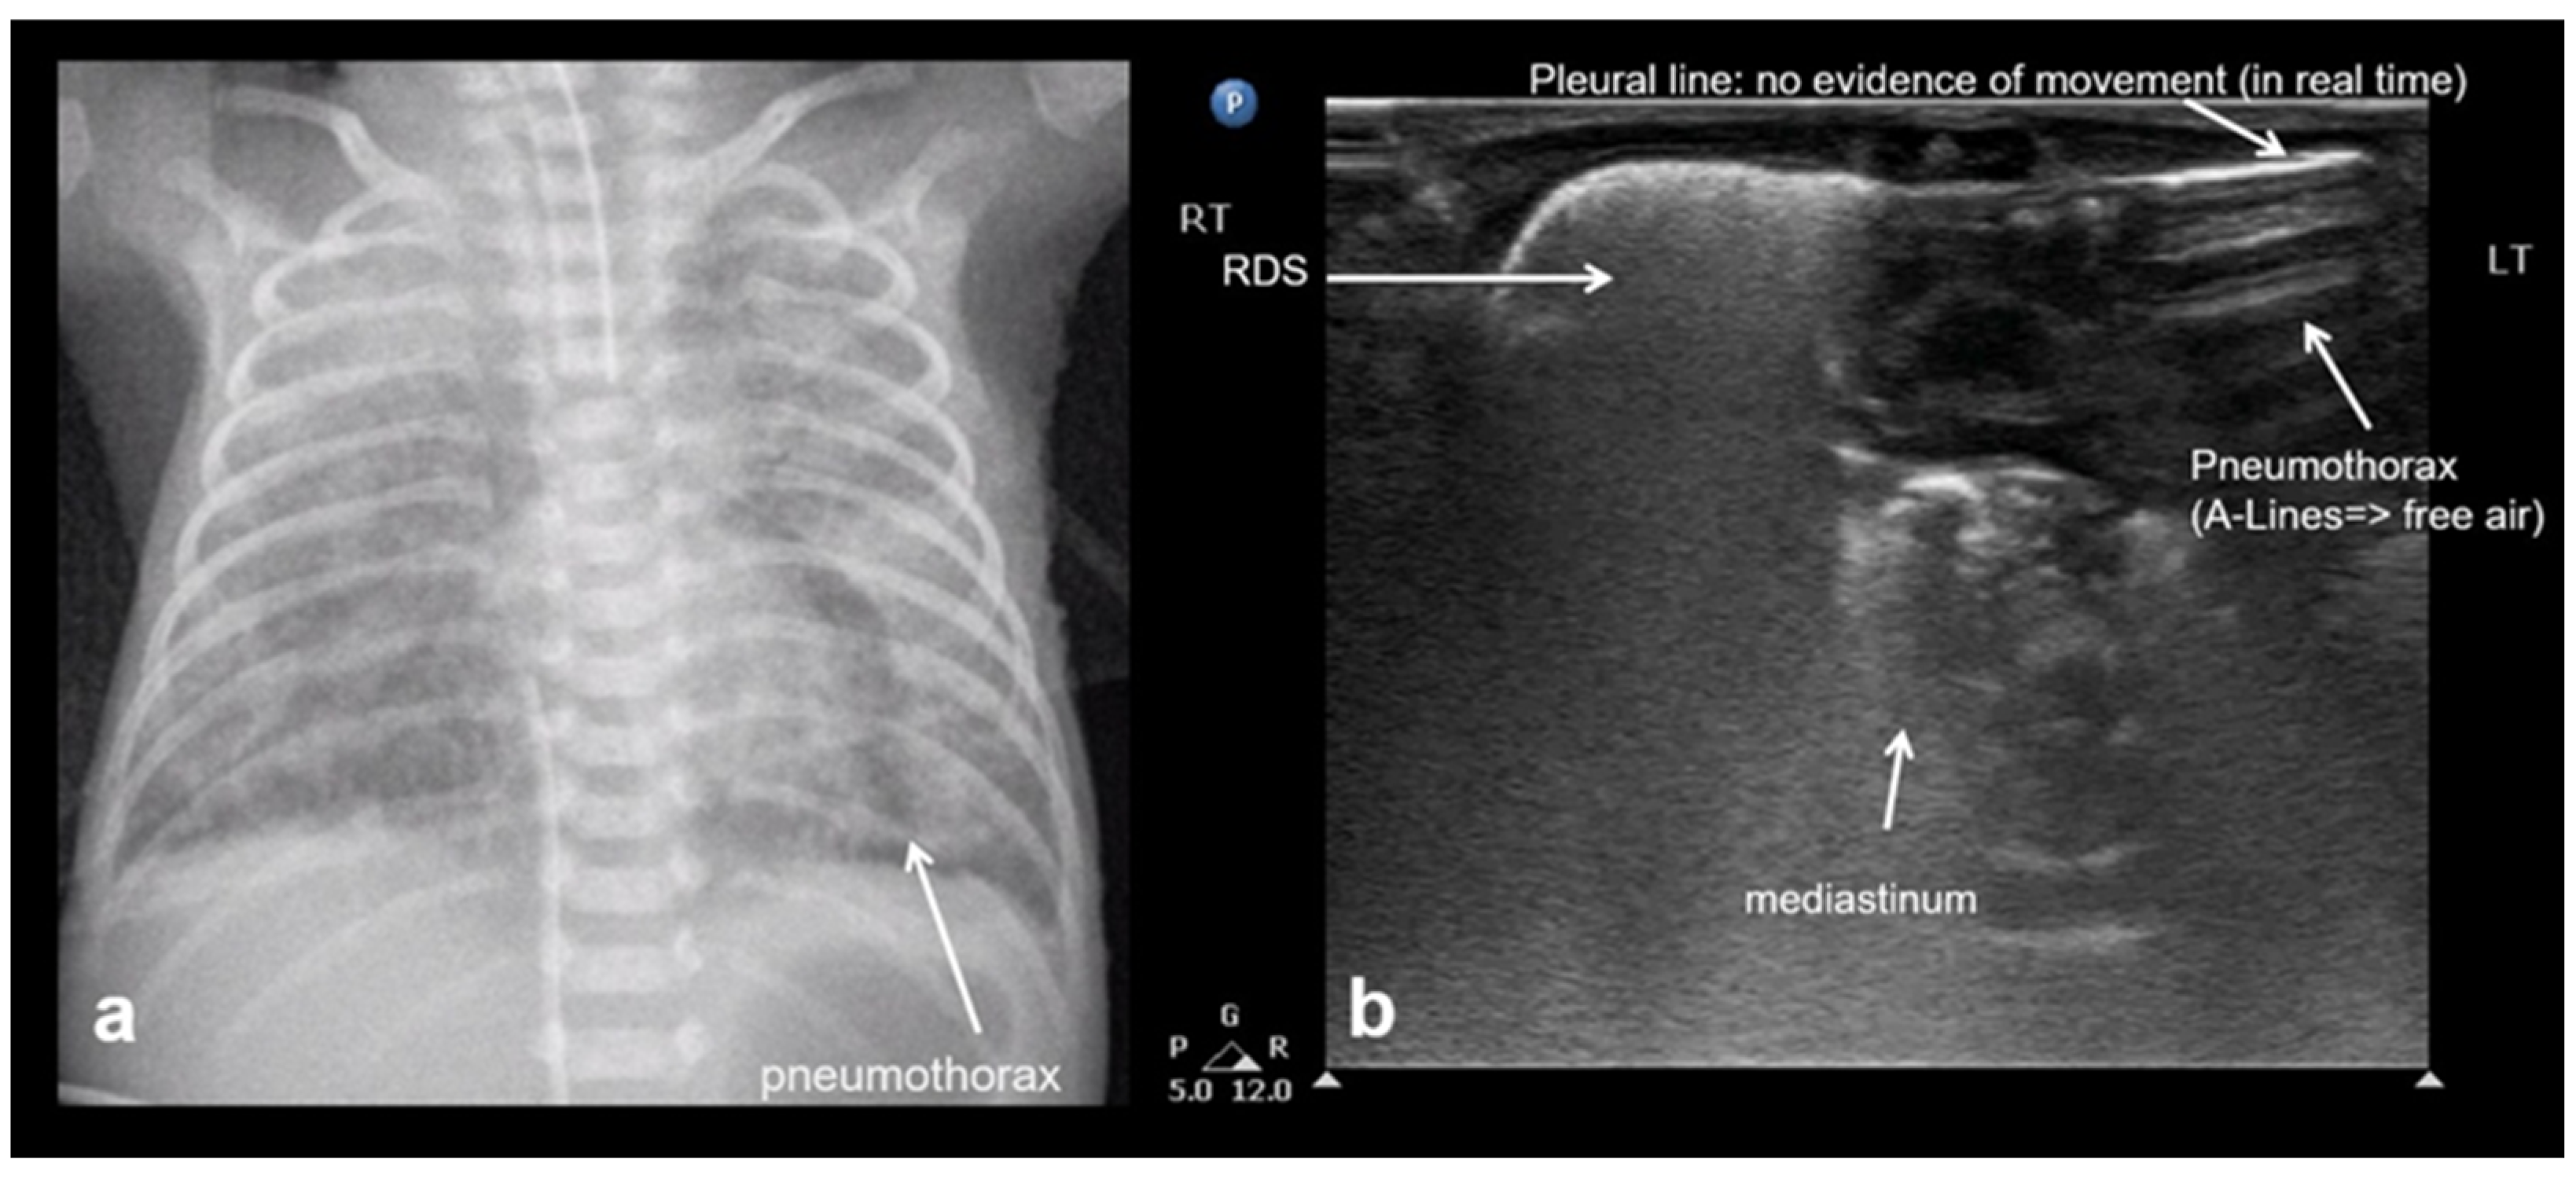

The hallmark sonographic feature of pneumothorax is the absence of lung sliding, reflecting a separation between the parietal and visceral pleura due to the presence of intrapleural air. This absence is typically accompanied by the loss of B-lines, which are reverberation artifacts dependent on intact pleural contact and subpleural aeration. Instead, A-lines are observed, indicating the presence of air in the pleural space without lung parenchymal motion. When pneumothorax is evaluated in M-mode, a characteristic stratosphere sign, or “barcode sign”, replaces the normal “sea-shore sign”, showing uniform horizontal lines without the granular pattern associated with moving lung tissue. The combination of the absence of lung sliding, the absence of B-lines, the presence of prominent A-lines, and the presence of the stratosphere sign strongly supports the diagnosis of pneumothorax and helps differentiate it from other causes of respiratory distress (Figure 22) [12,13,15,20,28,29,40,53].

Figure 22.

Pneumothorax: (a) CXR, (b) LUS.